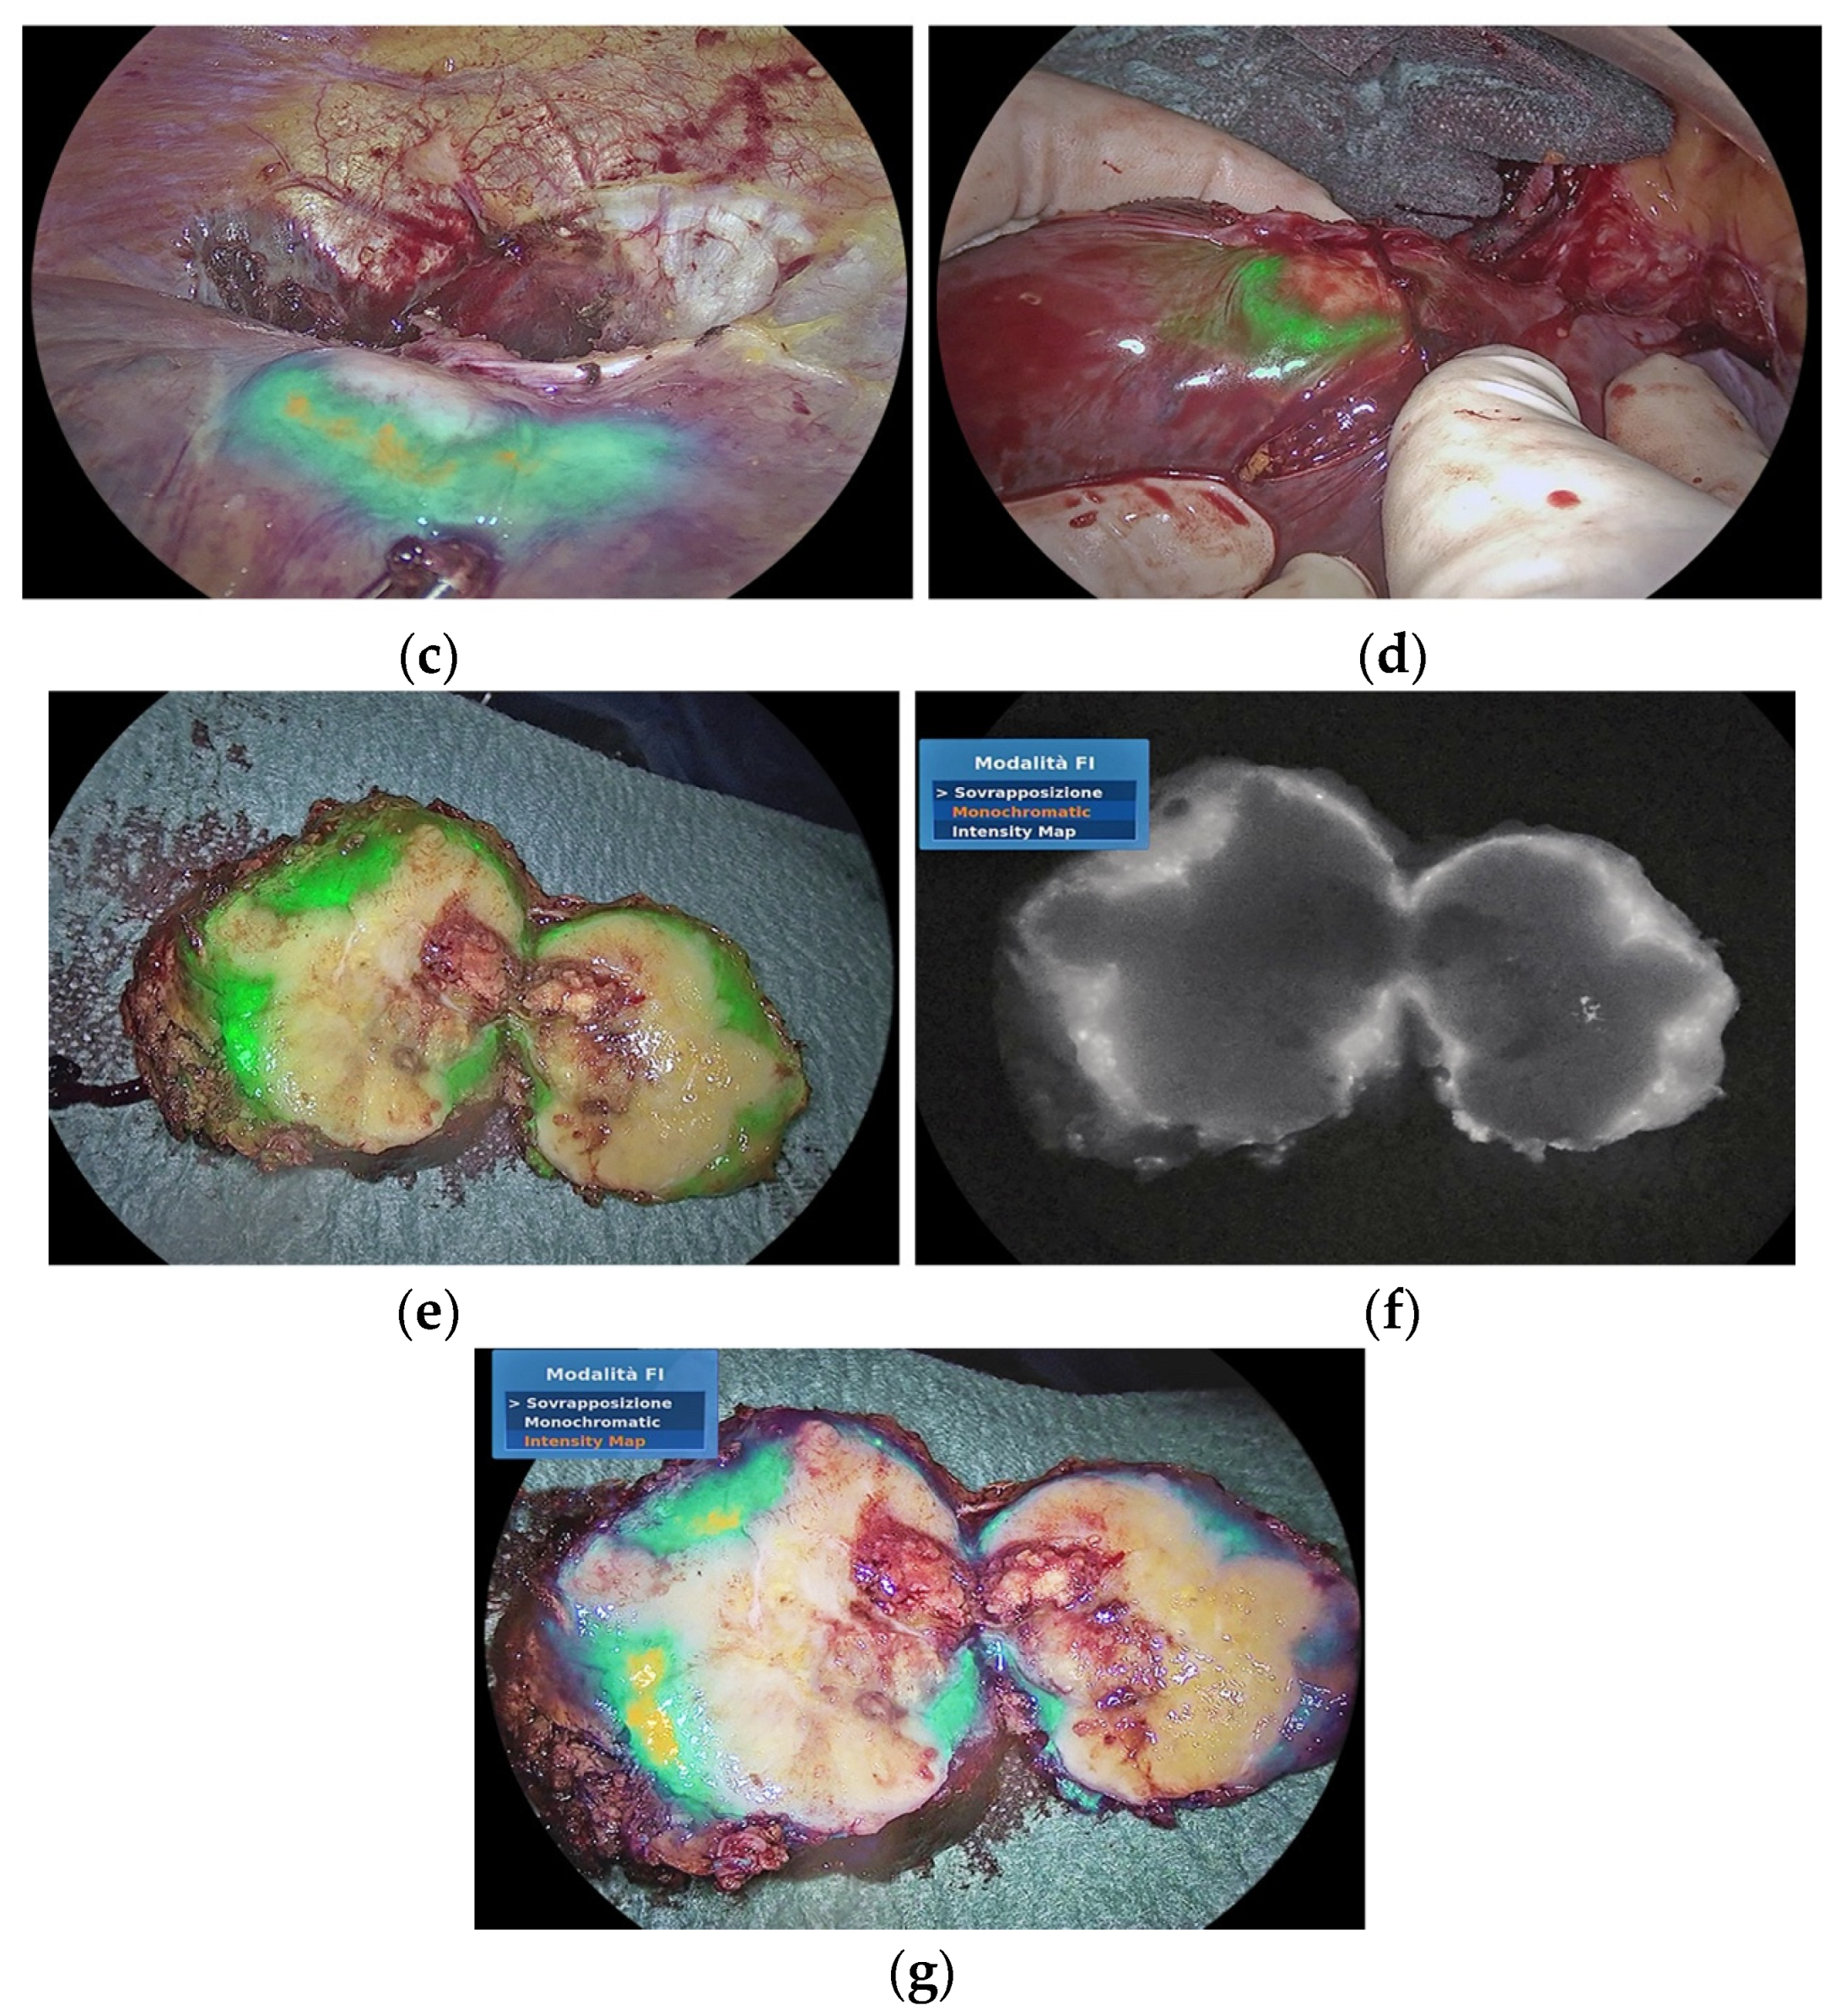

- Raimondo, D.; Maletta, M.; Malzoni, M.; Cosentino, F.; Scambia, G.; Falcone, F.; Coppola, M.; Turco, L.C.; Borghese, G.; Raffone, A.; et al. Indocyanine green fluorescence angiography after full-thickness bowel resection for rectosigmoid endometriosis: A multicentric experience with quantitative analysis. Int. J. Gynecol. Obstet. 2021, 158, 679–688. [Google Scholar] [CrossRef]